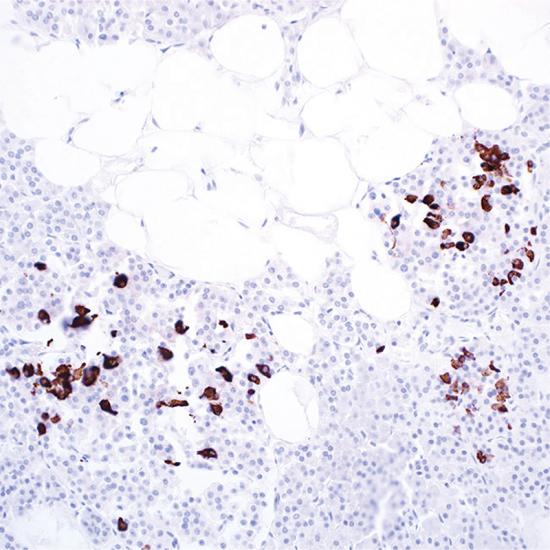

Somatostatin

Somatostatin抗體試劑(免疫組織化學(xué)) 閩廈械備20180282號

• 陽性部位:

細(xì)胞漿

• 陽性對照:

胰腺

兔單抗

• 克隆號:

EP130

生長抑素(Somatostain)是由116個氨基酸的大分子肽裂解而來的十四肽。主要作用是抑制垂體生長素(GH)的基礎(chǔ)分泌,也抑制腺垂體對多種刺激所引起的GH分泌反應(yīng)、包括運(yùn)動、進(jìn)食、應(yīng)激、低血糖等。